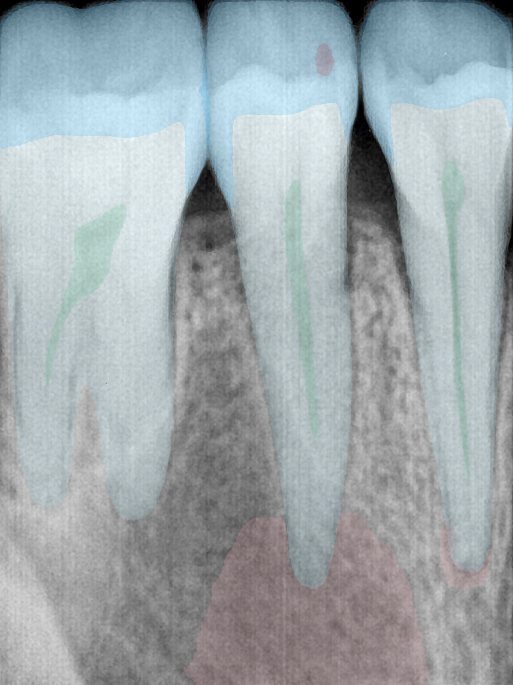

第二版算法问题测试

| 第一版 | 第二版 | 是否解决 | |

|---|---|---|---|

![]() | ![]() ![]() 边角识别有问题 龋齿识别不全 牙髓识别不全 | ![]() | 解决 |

![]() | ![]() 边角识别有问题 识别信息有误 自查(牙冠识别不全) | ![]() | 解决 |

![]() | ![]() ![]() 边角识别有误 大范围填充识别遗漏 | ![]() | 解决 |

![]() | ![]() 识别信息不全 | ![]() | 解决 |

![]() | ![]() ![]() 边角问题 牙胶识别不全 牙冠识别不全 | ![]() | 解决 |

![]() 换图片 | ![]() | ![]() 牙冠部分稍微白了一些就识别成小范围修补,部分判断异常 | 部分解决,修复类略敏感,牙冠部分稍微白了一些就识别成小范围修补,部分判断异常。 |

![]() | ![]() ![]() 牙冠识别不全 牙髓不全 根尖炎龋齿识别有误 | ![]() | 解决 |

![]() | ![]() | ![]() | 解决 |

![]() 换图片 | ![]() | ![]() | 解决 |

![]() | ![]() 牙冠识别有误 | ![]() | 解决 |

![]() 换图片 | ![]() ![]() 边角识别有误 | ![]() 修复类敏感 | 部分解决,图像过白,导致修复类判断异常。 |

![]() 换图片 | ![]() 牙冠识别不全 | ![]() 修复类敏感 | 部分解决,图像过白,导致修复类判断异常 |

结论:修复类出现了不鲁棒的情况,后续需要加入轮廓的扩充数据进行增强。